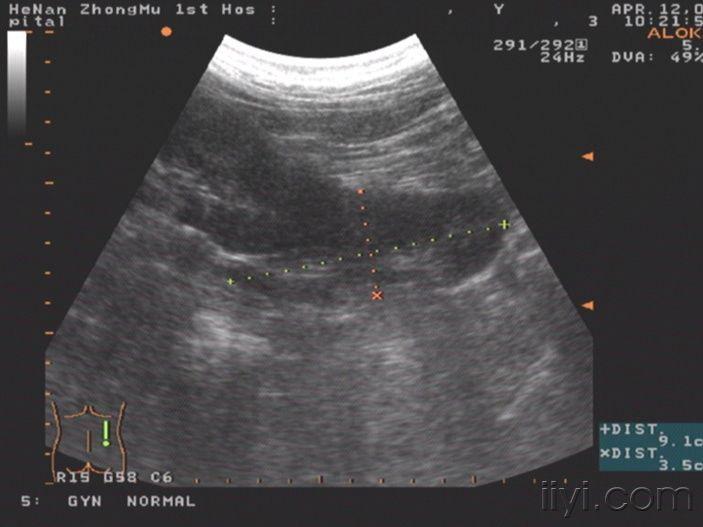

【讨论】给大家几幅超声图片看看 - 超声医学讨论版 - 爱爱医医学论坛

图片尺寸500x375